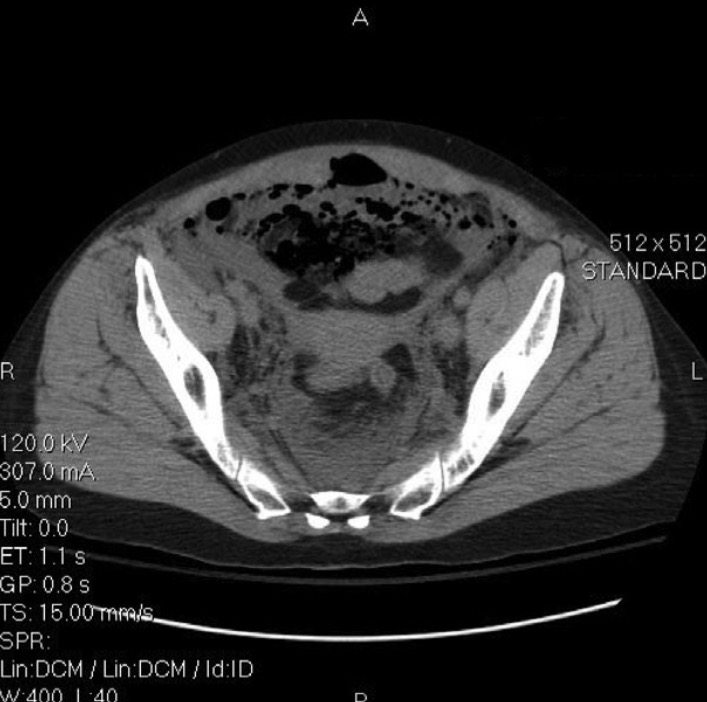

Figure 2. Компьютерная томография брюшной полости и таза, демонстрирующая значительное количество воздуха и жидкости располагающихся внебрюшинно кпереди от мочевого пузыря.